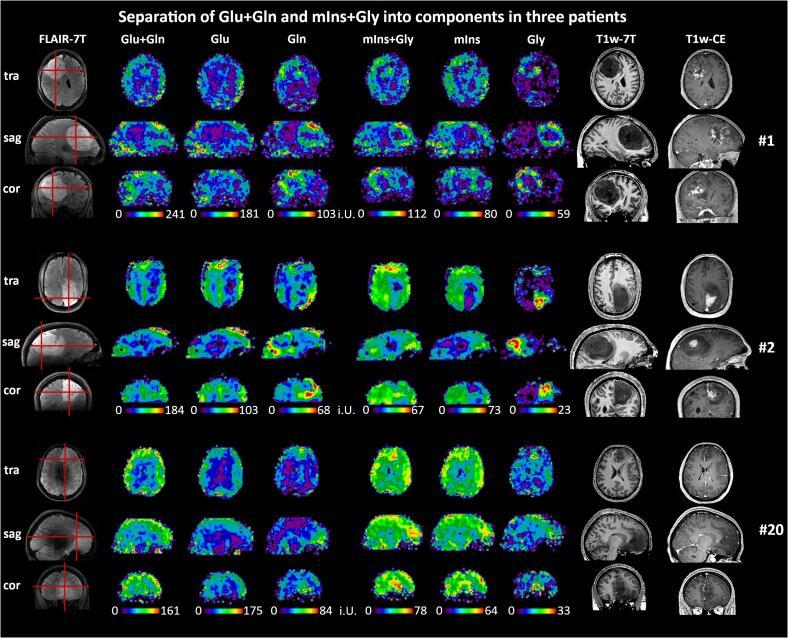

We preoperatively measured 23 patients with histologically verified HGGs (17 male, 8 female, age 53 ± 15) with an MRSI sequence based on concentric ring trajectories with a 64 × 64 × 39 measurement matrix, and a 3.4 × 3.4 × 3.4 mm nominal voxel volume in 15 min. Quantification used a basis-set of 17 components including N-acetyl-aspartate (NAA), total choline (tCho), total creatine (tCr), glutamate (Glu), glutamine (Gln), glycine (Gly) and 2-hydroxyglutarate (2HG). The resultant metabolic images were evaluated for their reliability as well as their quality and compared to spatially segmented tumor regions-of-interest (necrosis, contrast-enhanced, non-contrast enhanced + edema, peritumoral) based on clinical data and also compared to histopathology (e.g., grade, IDH-status).

Eighteen of the patient measurements were considered usable. In these patients, ten metabolites were quantified with acceptable quality. Gln, Gly, and tCho were increased and NAA and tCr decreased in nearly all tumor regions, with other metabolites such as serine, showing mixed trends. Overall, there was a reliable characterization of metabolic tumor areas. We also found heterogeneity in the metabolic images often continued into the peritumoral region. While 2HG could not be satisfyingly quantified, we found an increase of Glu in the contrast-enhancing region of IDH-wildtype HGGs and a decrease of Glu in IDH1-mutant HGGs.

We successfully demonstrated high-resolution 7T 3D-MRSI in HGG patients, showing metabolic differences between tumor regions and peritumoral tissue for multiple metabolites. Increases of tCho, Gln (related to tumor metabolism), Gly (related to tumor proliferation), as well as decreases in NAA, tCr, and others, corresponded very well to clinical tumor segmentation, but were more heterogeneous and often extended into the peritumoral region.

我们术前对 23 例经组织学证实的 HGG 患者(17 名男性,8 名女性,年龄 53±15 岁)进行了测量,使用基于同心环轨迹的 MRSI 序列,测量矩阵为 64×64×39,体素体积为 3.4×3.4×3.4mm,15 分钟内完成。定量分析使用包括 N-乙酰天冬氨酸(NAA)、总胆碱(tCho)、总肌酸(tCr)、谷氨酸(Glu)、谷氨酰胺(Gln)、甘氨酸(Gly)和 2-羟基戊二酸(2HG)在内的 17 个成分的基集。对代谢图像的可靠性、质量以及基于临床数据的肿瘤区域(坏死、增强、非增强+水肿、肿瘤周围)进行了评估,并与组织病理学(如分级、IDH 状态)进行了比较。

18 名患者的测量值被认为是可用的。在这些患者中,有 10 种代谢物的定量质量可以接受。几乎所有肿瘤区域的 Gln、Gly 和 tCho 增加,NAA 和 tCr 减少,而其他代谢物如丝氨酸则呈现混合趋势。总的来说,代谢肿瘤区域的特征具有可靠性。我们还发现代谢图像中的异质性通常延伸到肿瘤周围区域。虽然 2HG 不能令人满意地定量,但我们发现 IDH 野生型 HGG 中增强区的 Glu 增加,而 IDH1 突变型 HGG 中 Glu 减少。

我们成功地在 HGG 患者中展示了高分辨率 7T 3D-MRSI,显示了多种代谢物在肿瘤区域与肿瘤周围组织之间的代谢差异。tCho、Gln(与肿瘤代谢有关)、Gly(与肿瘤增殖有关)的增加,以及 NAA、tCr 和其他代谢物的减少,与临床肿瘤分割非常吻合,但更具异质性,且常常延伸至肿瘤周围区域。